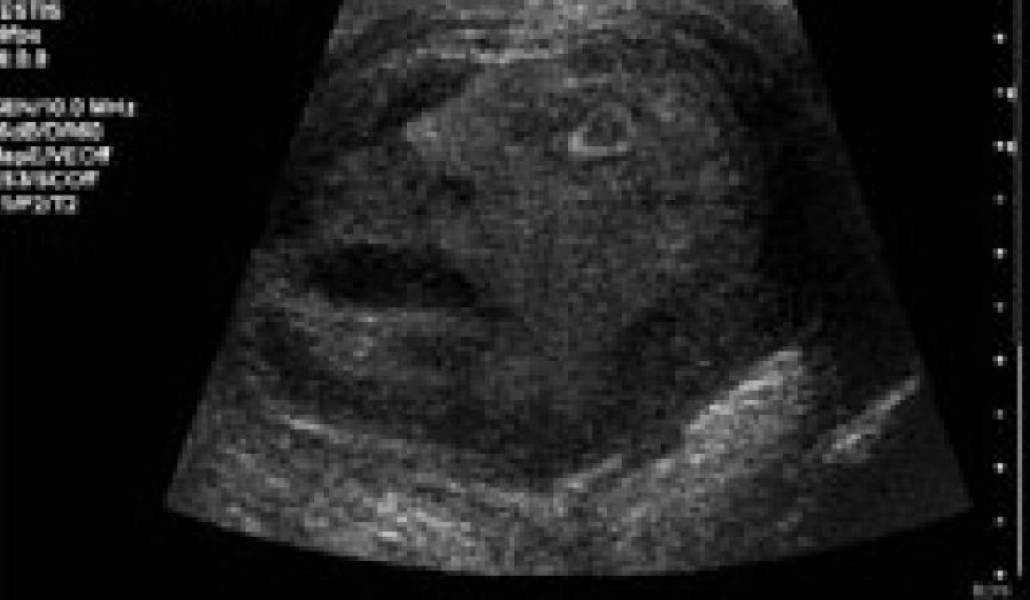

Опухоль в виде лица человека

Во время диагностирования опухоли яичка сотрудники Медицинской школы Университета Квинс поразились тому, ЧТО возникло вдруг на экране аппарата. Оттуда на них смотрело четко различимое человеческое лицо.

По словам специалистов, "лицо" имело такое выражение, будто кто-то кричал в агонии. Его рот был раскрыт, а один глаз выбит.

Известно, что снимок принадлежит 45-летнему мужчине, который обратился к врачу с жалобами на дискомфорт.

Специалисты выявили у него доброкачественное новообразование размером в 6 сантиметров, Именно это новообразование "гримасничало" во время ультразвукового исследования. В какие-либо знаки свыше медики верить отказались, поэтому пришлось удалить пораженный орган. Тем не менее, врачи признались, им ни разу не приходилось видеть подобную опухоль за всю свою врачебную практику, пишет The Star.